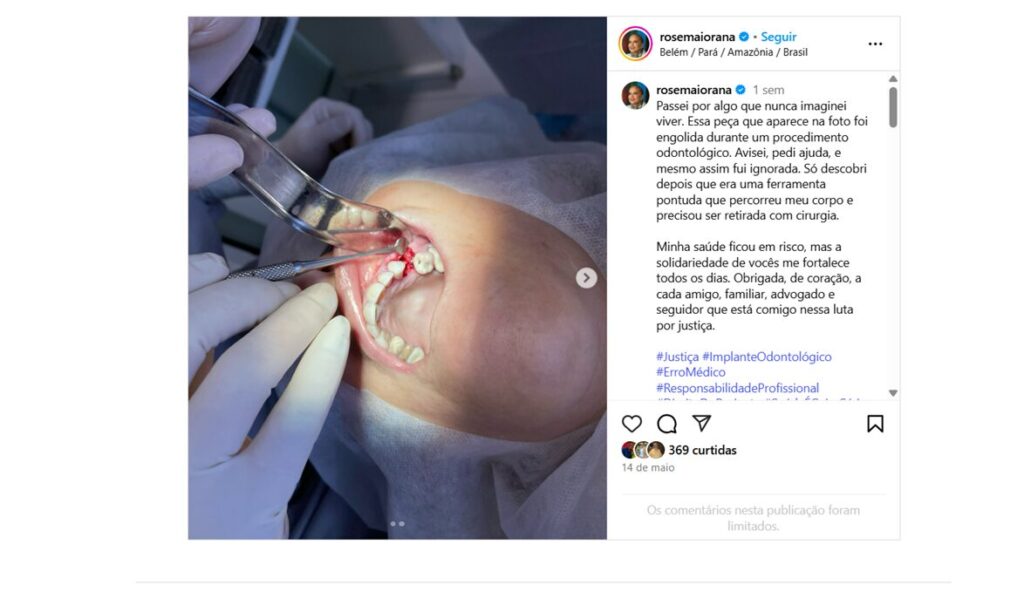

Em seu perfil no Instagram, Rose relatou:

“Passei por algo que nunca imaginei viver. Essa peça que aparece na foto foi engolida durante um procedimento odontológico. Avisei, pedi ajuda, e mesmo assim fui ignorada. Só descobri depois que era uma ferramenta pontuda que percorreu meu corpo e precisou ser retirada com cirurgia.”

A empresária afirmou ter informado à equipe odontológica, no momento do procedimento, que algo estranho havia sido engolido, mas que suas queixas foram desconsideradas. O relato ganhou repercussão nas redes sociais, levando a Clínica Lavareda a emitir uma nota oficial negando veementemente qualquer envolvimento com o ocorrido.

VEJA FOTOS: